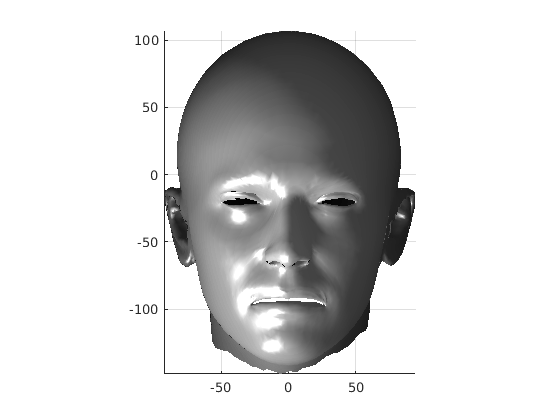

Fig. 9 shows examples of the fitted model (trained on FRGC data) on the first four subjects in our Headspace training set. Note that the mean of the landmarks in the sparse model is centred on the orgin, and so the scan data is moved towards that and becomes frontal in pose. We note that other researchers [28] have used 3D landmark localisation to find the head, but often this only includes landmarks that are relatively easy to localise, namely inner eye corners and nose. Localising more landmarks over a wider facial area has a number of advantage in terms of cropping, pose normalisation and global 3D template warping, all of which are described later.

The template mesh is then warped in a global affine sense, as shown in Fig. 27 to minimise the least-squares error between the two sets of landmarks, when the head scan is fixed in its canonical poose. After this initial stage, landmarks and pseudo-landmarks are used in the same way as any other mesh vertex, as they are potentially noisy, as seen in earlier results analysis. This contrasts with Amberg et al’s [11] approach where the influence of landmarks is gradually faded out.

Following this, OSNR ICP iterates over a set of decreasing mesh stiffnesses (typically 10), until the registration between the template and the scan is below some error or a maximum number of iterations is reached. Figure 28 shows a selection of template warp results. The template appears to be accurately warped onto the scan, at least in the normal direction of the surfaces, it is not possible to see error tangential to the surface. Furthermore, we have noted errors on some scans on the ears. To improve these we need a method of automatically landmarking the ears, which is an area for further work.

The first two modes of head variation are shown in figures 29 and 30. These include the cranial height / facial angle mode and the (almost) pure size mode, as seen in the sagittal profile model.